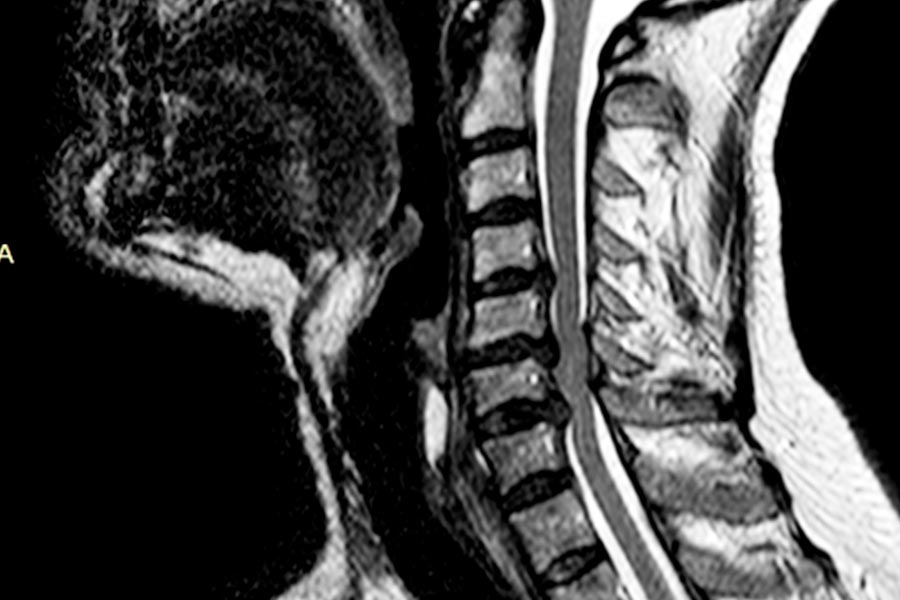

Caso de extrema dificultad en el que podemos ver a un paciente con dolor crónico cervical, parentesias MMSS y hormigueo en los miembros superiores.